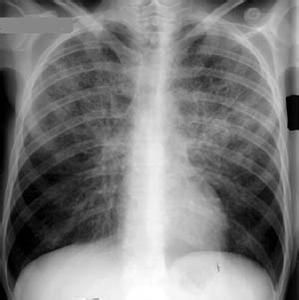

肺囊蟲性肺炎